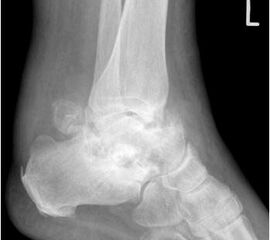

• Primäre oder posttraumatische Arthrose des OSG und USG (Abbildung 1, Abbildung 2).

• Revision einer gescheiterten Fusion des OSG/ USG (Abbildung 3, Abbildung 4).